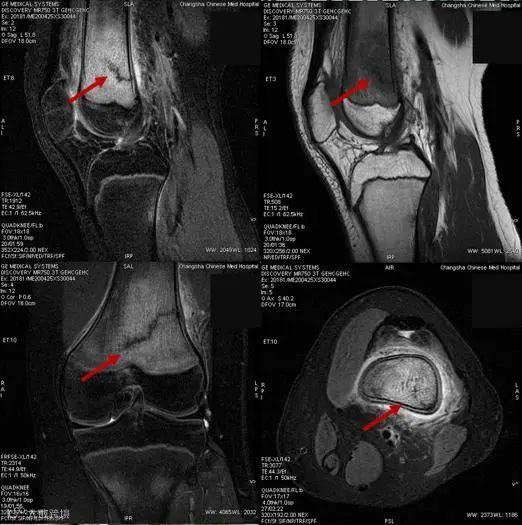

导读:近3天来,科室陆续诊断了7例 “应力性骨”患者 ,这7名患者有一个共同点——都是14~15岁的青少年。放射科主任罗春提醒,随着一些学生陆续返校,突然增大的运动量,容易导致青少年出现应力性骨折。

15岁的罗同学,因“右膝关节肿痛,加重1天”入院,在行膝关节磁共振成像检查时,发现“右侧股骨下段骨折并广泛骨髓水肿”。通过仔细询问病史发现,这名新近返校的初三学生,因邻近中考需要参加体育考试,每天都进行了一定强度的体育训练,最近几天出现膝关节疼痛明显加重,于是罗同学的妈妈带他到医院就诊。

很快,又有三名同学陆续来院就诊,他们的情况与罗同学完全一样,

都是14~15岁的初中生,在学校参加跑步等体育锻炼后出现膝关节疼痛,

并加重后就诊,经磁共振成像检查,被诊断为应力性骨折。

影像学检查能有效诊断应力性骨折,轻-中度应力反应早期X射线片表现可能不明显,但磁共振成像能有效发现骨膜及骨髓水肿。严重应力反应及应力性骨折在X射线片可见骨皮质增厚甚至骨折线影,而磁共振成像对骨膜与骨髓水肿范围显示更清晰。出现相关症状时,应及时进行磁共振成像检查。